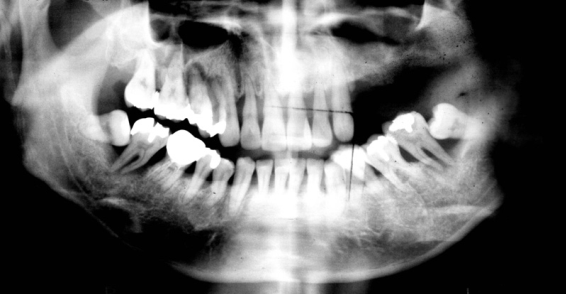

これ(下写真↓)は私の歯のレントゲン写真です。

ご参考までに、私の歯の写真も見てみましょう。

2本の前歯のはっきりした白いものは、セラミック人工歯です。

向かって右側の奥歯2本が倒れるようにあるのがよくわかります。

ちなみに、これを抜いて現在、吉本歯科医院にてインプラント治療中です(^^)。

歯が骨から抜けたままにしておくと、このように手前に倒れてきます。

そうなると噛むことができなくなり左と右など全体のかみ合わせのバランスが崩れてきます。

このレントゲン写真をご覧下さい。

スポーツをされている方です。

こういう症例は実は本当に難しいんです。

この写真を見ると、ほとんどきれいな歯なんです。

白く光る部分がほとんどありません。

ところが、1本だけ、2本だけ、歯科治療をされていました。

そして、この歯は根っこの治療までされています。

ほとんど虫歯なんかない。

治療なんかしたことすらない。

でも必ずいつも同じ歯が何度も悪くなる。

左上の歯は神経まで治療されています。